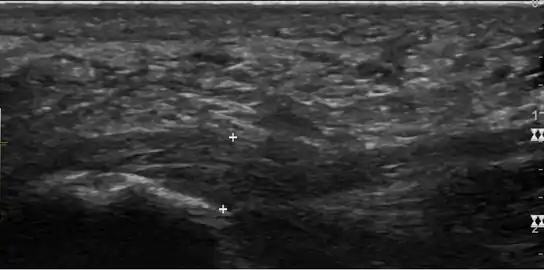

a)Ultrasonographic finding of plantar fasciitis b)normal sonographic finding

a)Ultrasonographic finding of plantar fasciitis b)normal sonographic finding Heel bone with heel spur

Heel bone with heel spur Thickened plantar fascia in ultrasound

Thickened plantar fascia in ultrasound

Imaging

Medical imaging is not routinely needed. It is expensive and does not typically change how plantar fasciitis is managed.[15] When the diagnosis is not clinically apparent, lateral view X-rays of the ankle are the recommended imaging modality to assess for other causes of heel pain, such as stress fractures or bone spur development.[7]

The plantar fascia has three fascicles-the central fascicle being the thickest at 4 mm, the lateral fascicle at 2 mm, and the medial less than a millimeter thick.[18] In theory, plantar fasciitis becomes more likely as the plantar fascia's thickness at the calcaneal insertion increases. A thickness of more than 4.5 mm ultrasound and 4 mm on MRI are useful for diagnosis.[19] Other imaging findings, such as thickening of the plantar aponeurosis, are nonspecific and have limited usefulness in diagnosing plantar fasciitis.[13]